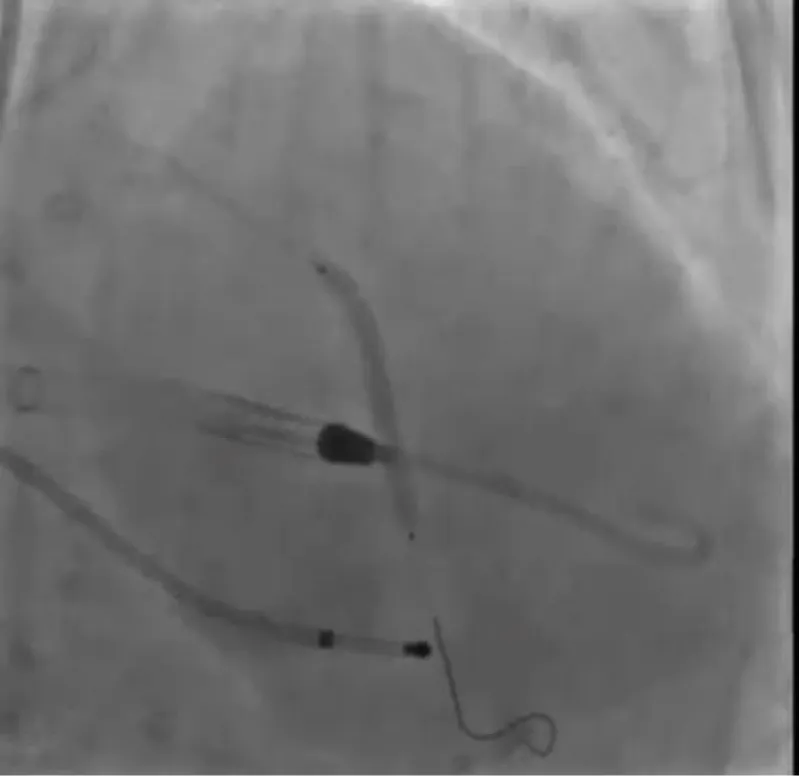

The clinical case concerns an 81-year-old woman with a history of systemic arterial hypertension, hypercholesterolemia, paroxysmal atrial fibrillation, chronic kidney disease, iron-deficiency anemia, and bilateral carotid atheromatosis for which she underwent a Carotid Endarterectomy (CEA) procedure. Additionally, she had a history of breast carcinoma, treated with surgery, subsequent chemotherapy, and ongoing Letrozole therapy. In 2019, the patient presented to the emergency department due to exertional dyspnea and low-threshold angina. During hospitalization, high average ventricular response (109 BPM) atrial fibrillation was diagnosed. Routine lab tests showed rising of hsTN-I (peak 800 pg/dL) and pro-BNP (peak 2476 pg/mL) and anemia Hb 9.1 g/dL. Echocardiography revealed severe depression of the left ventricular function (ejection fraction of 30%, with antero-apical akinesia) and low-flow-low-gradient aortic stenosis (mean gradient of 26 mmHg and AVAi of 0.5 cmq/m2 and SVi 29 mL/m2). So it was performed a Dobutamine stress Echo showed a rise of SVi up to 38 mL/m2 and a mean aortic gradient of up to 48 mmHg. Coronary angiography showed the right dominant coronary artery, of good caliber and course, with no angiographically significant lesions (Figure 1). The Left Main artery, with good caliber, had a 90% calcific stenosis at the distal segment, involving the proximal segment of the Left Anterior Descending artery. The Left Circumflex artery, with good caliber and course, presented a 30% ostial stenosis. The Intermediate Branch, with good caliber and course, showed 80% stenosis at the proximal segment (Figure 2). The Left Anterior Descending artery, also of good caliber and course, was diffusely atherosclerotic with a long, severely calcific 80% stenosis at the mid-distal segment (Figure 3). Therefore, the case was discussed by a multidisciplinary Heart team at our center. The STS score calculated indicated a mortality risk of 11.4%. Due to this high risk, surgical treatment was not considered, and the patient underwent a four-step percutaneous intervention. Before the intervention, a CT angiography was performed, revealing an aortic annulus area of 433.2 mm2, a perimeter of 75.3 mm, and a coronary height from the annulus of 10 mm. The right common femoral artery mean diameter was 6.1 mm2 and the external iliac artery was 8.4 mm2 with moderate tortuosity without significant calcification (Figure 4-6). Therefore, a 23 mm Edwards Sapien 3 valve was chosen. Our strategy consisted of 4 steps:

Figure 1: Right dominant coronary artery, of good caliber and course, with no angiographically significant lesions.